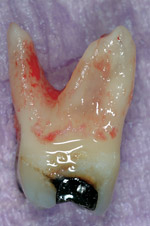

Figure 1 shows a radiograph of a typical maxillary first molar. Upon extraction, the apical anatomy was immediately studied and photographed under a global microscope (Figure 2, Figure 3, Figure 4, Figure 5 and Figure 6). That is a take-home lesson; the extracted teeth should be studied with loupes or microscopes. These photographs demonstrate an important lesson. The two-dimensional radiograph shows three roots. In reality, however, a significant percentage of maxillary first and third molars—80% in some studies—have four roots and four or more canals. 1,2 While the MB and MP (MB-2) roots are usually fused, their morphology is unique. For diagnostic, access, and shaping purposes, it is safer to think of them as separate roots. Wisdom teeth often exaggerate the anatomic features of first and second molars, and a significant percentage of maxillary third molars have four distinct roots. The author's personal bias is to consider most maxillary first the radiographic apex of the tooth. The use of the radiographic root apex for use as the reference point for measuring the apical extent of the root filling is the common standard, yet has been criticized because of the poor correlation between the location of this point and the actual canal foramen. 5 The illustrations used in advertising and manufacturer's "tip cards" only further the notion of simple foramen anatomy. While simple anatomy is often the case with incisor teeth, a quick perusal of the posterior teeth in Brown and Herbransen's Dental Anatomy & 3D Interactive Tooth Atlas demonstrates that a significant portion of the foramen exit short of the apex and have multiple foramina. 6 The same extracted tooth in Figure 2 demonstrates that the palatal foramen is more than a millimeter short of the radiographic apex. If this tooth were filled to the constriction, which for arguments sake is 0.75 mm from the foramen, a straight-on radiograph would depict the fill as being at least 2 mm "short."

Fig. 2 Facial view of Fig. 1 immediately after extraction.

Figure 2

Fig. 3 Mesial view of Figure 1 shows true three-dimensional anatomy of the mesial root.

Figure 3

Fig. 4 High-magnification apical view of Figure 1 shows correct apical anatomy. Note the large palatal foramen is at least 1 mm short of the radiographic apex (arrow).

Figure 4

Fig. 5 High-magnification apical view of Figure 1 shows correct apical anatomy. Note the large palatal foramen is at least 1 mm short of the radiographic apex (green arrow).

Figure 5

Fig. 6 High-magnification view of mesio–buccal (blue arrow) and mesio–palatal (red arrow) roots. Small blue arrow marks another foramen emanating from the MB system.

Figure 6